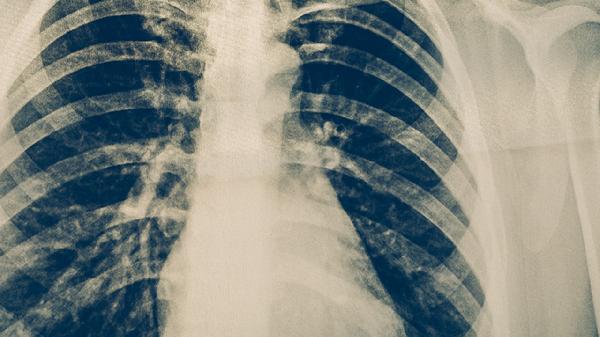

治疗初期每月进行痰涂片和培养检查,后期每2-3个月复查。胸部CT每6个月评估病灶变化,出现新空洞或播散灶需调整方案。药物浓度监测可优化给药剂量,血常规和肝肾功能每月检测。治疗结束后仍需随访2年,每半年进行1次痰菌检查。